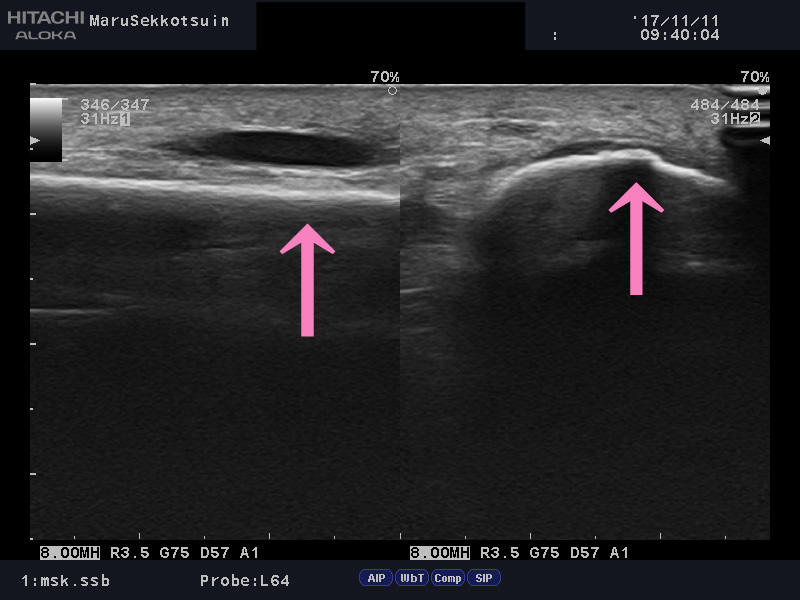

そして確認でエコー検査でございます。

そして結果は「シンスプリント(脛骨過労性骨膜炎)」

エコー検査でも脛骨表面にも異変が診られ、

「疲労骨折」の疑いもある為、しばらく安静加療となりました。